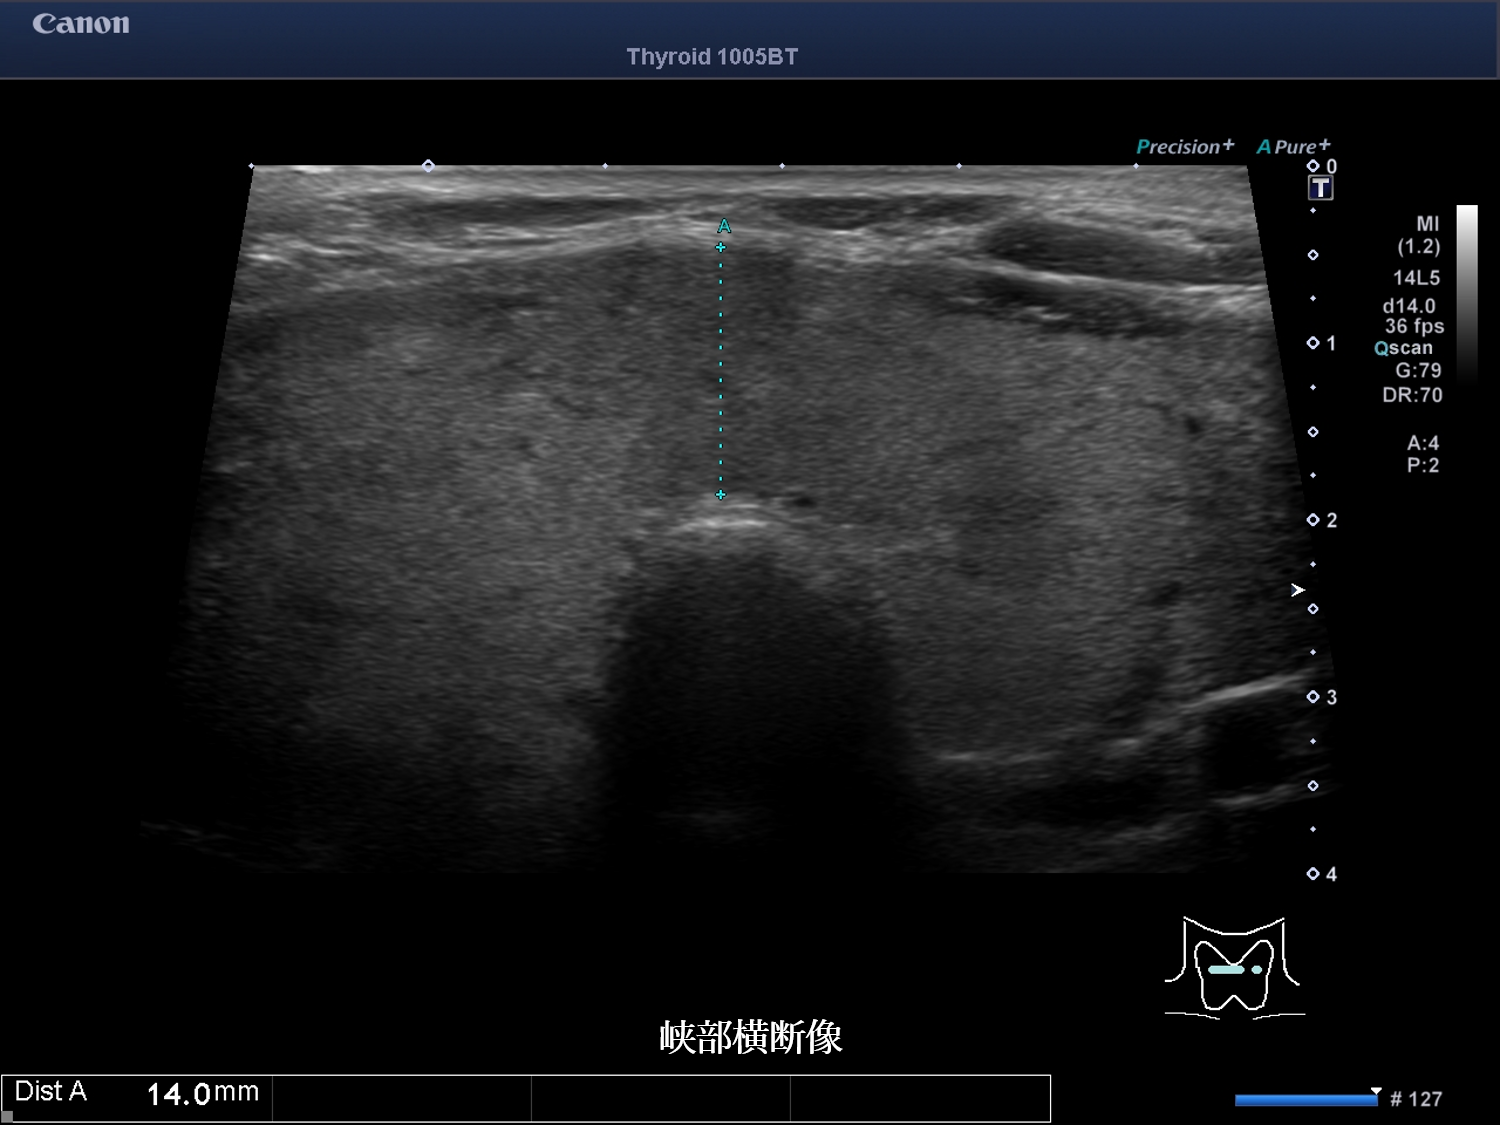

甲状腺超音波画像 画像1(No20-21_1)画像2(No20-21_2)画像3(No20-21_3)